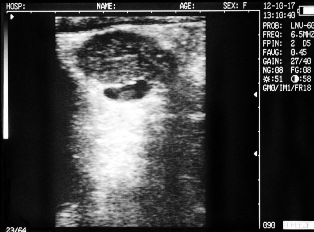

Uterine horn heifers